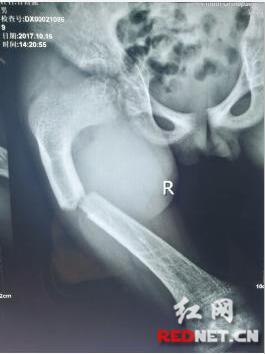

小博强摔伤时X光片

9岁的小博强不慎于10月16日在学校一下坡处滑倒,右大腿无法动弹并伴有持续性疼痛,让他止不住哇哇大哭,老师紧急将其送往娄底市骨伤医院。入院后,完善相关检查,诊断为“右股骨骨折”,遂收住髋股膝胫科。“怎么的了啊,我的崽啊,怎么摔的那么严重啦…”患儿的妈妈哭着赶到医院。据悉,患儿家境贫苦,因其母腿部患有先天畸形,家中四姊妹有三个大腿是先天畸形。了解到小博强家庭困难,医院决定为其开辟绿色通道,因有先天畸形,院领导召集专家会诊并制定合理的治疗方案,旨在竭力为其提供高超的技术和优质的服务。在欠费的情况下,医院采取了传统中医手法复位+小夹板固定治疗,手法复位后骨折端对位对线解剖复位,免除了手术治疗带来的痛苦,避免了手术治疗的高费用及愈后再次手术带来的损伤。考虑到患儿年龄小、好动,且患儿骨折断端在股骨畸形的应力处,随时有移位的可能,科室采用皮牵引配合小夹板治疗。为促进患儿骨痂生长,医院坚持给予中药和物理治疗。闲暇之余,髋股膝胫科的护士姐妹们不忘到病房和小博强聊聊天,将自己好吃的东西分享给他,让小博强在医院的每一天都忘记病痛过的开心。